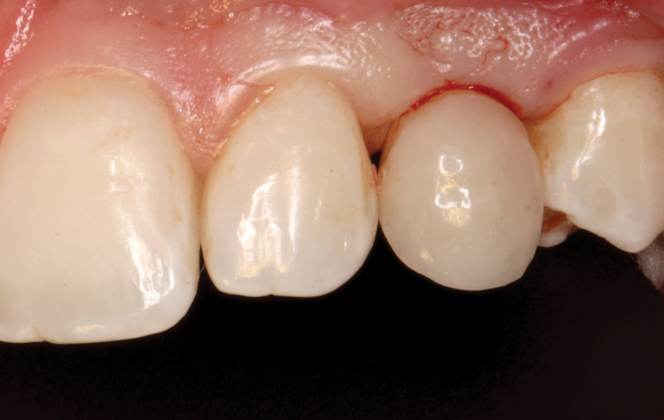

(38.) The opaqued titanium provisional abutment was gently tightened onto the implant.

Figure 38

(39.) The composite tooth shell was modified to fit around the abutment, positioned intraorally, and bonded to the abutment with flowable composite in the incisal half.

Figure 39